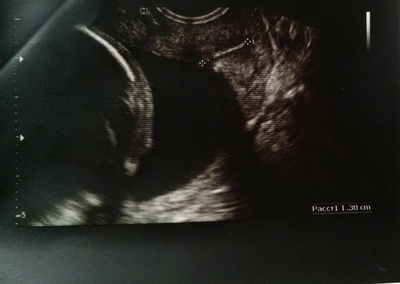

Единственный и в общем-то, "золотой стандарт диагностики" - трансвагинальное УЗИ. Относительно ИЦН для нас важен второй скрининг - именно в 18 недель оценивается шейка матки.

Если у женщины по первому скринингу шейку намерили менее 30 мм - это повод для настороженности в отношении ИЦН. Таким женщинам можно рекомендовать цервикометрию в 16 недель. Как и женщинам с ИЦН и/или преждевременными родами в анамнезе.

Критерии постановки диагноза:

- Бессимптомное укорочение длины сомкнутых стенок цервикального канала менее 25 мм.

- Дилатация цервикального канала более 10 мм на всём протяжении.